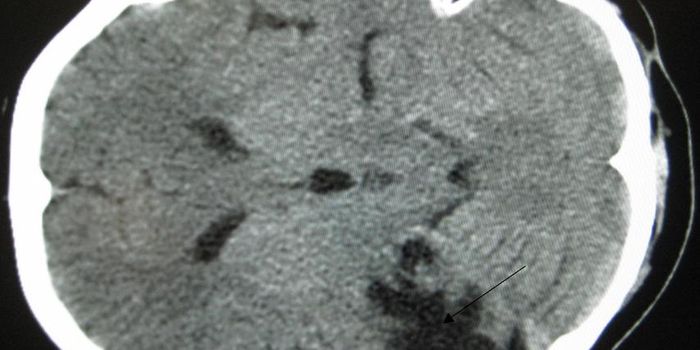

Read the latest articles about newly released neuroscience research and advances in experimental techniques. Topics include research news in neuroscience, neurology, psychology, brain science and cognitive sciences.